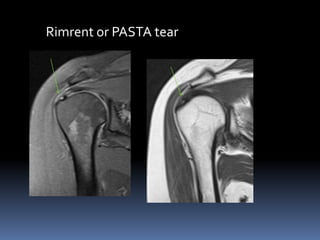

Rimrent or PASTA tear

 A partial tear that extends to articular surface

does not extent to bursal surface.